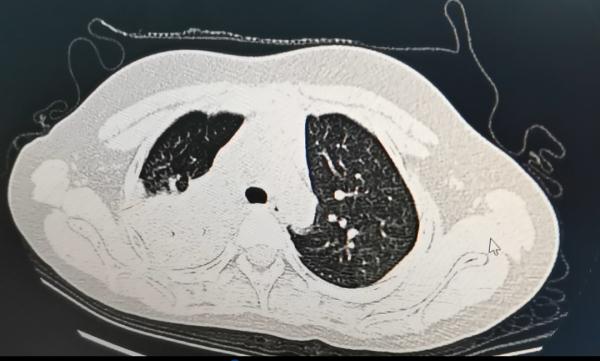

经过医生检查,孩子整个右肺大部分已经变成了白肺状,肺部存在病灶,经过检测确诊为支原体肺炎的感染。

2. 拍胸片或CT检查看肺部有无病变、严重程度如何,为下一步治疗提供重要参考依据;